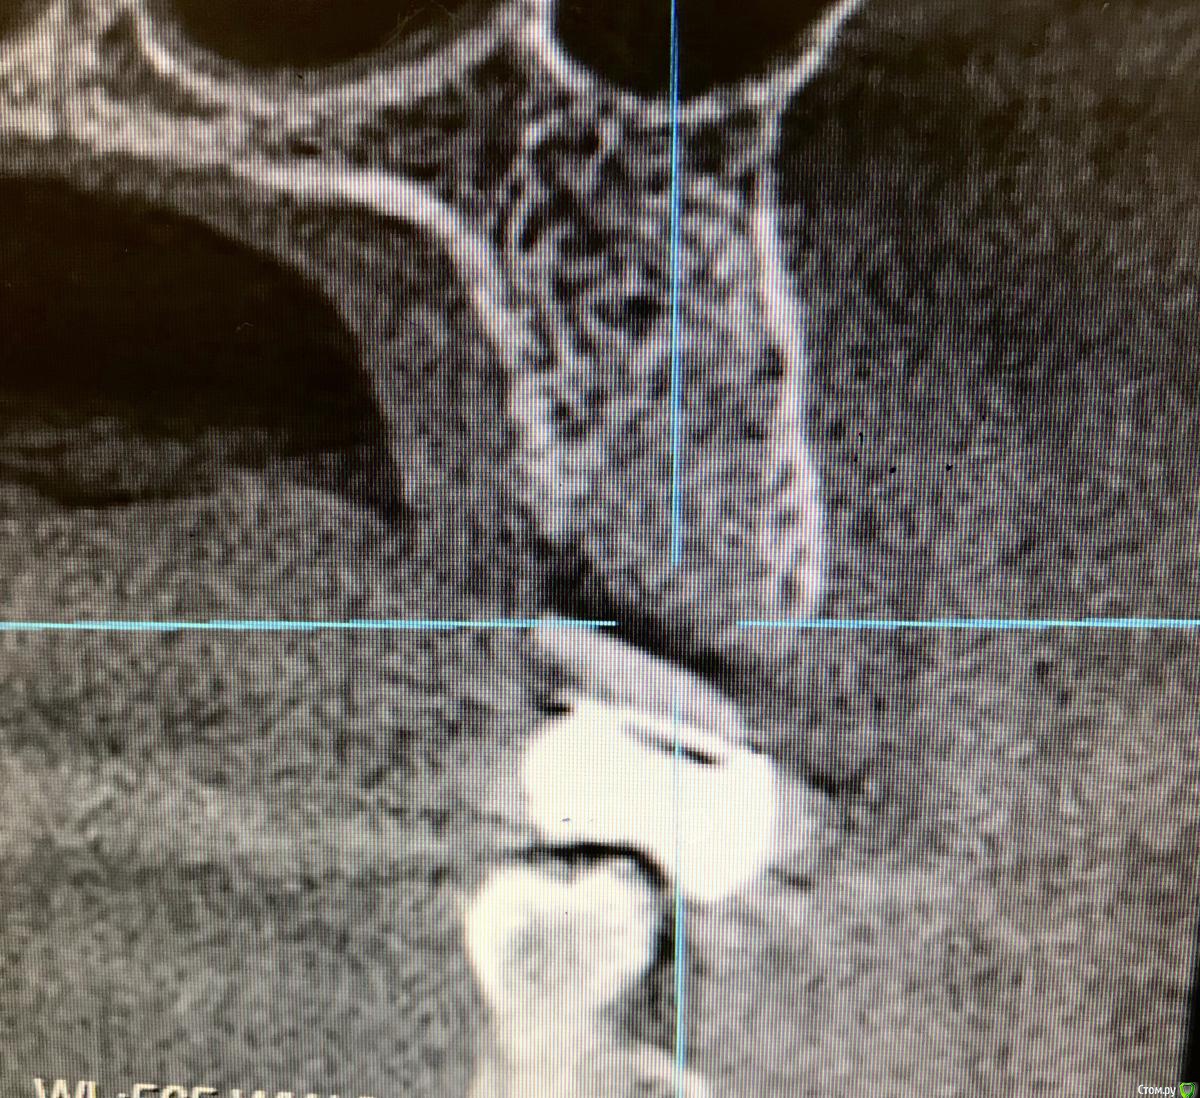

annda Опубликовано 7 августа, 2018 Поделиться Опубликовано 7 августа, 2018 (изменено) Тоже попробовала.Застарелый перелом корня.Два свища на момент приема.Удаление всего,спилила на коронковом фрагменте до связки,канал закрыла IRMом,в дефект порошок Лилпласт на АPRF ,обратно фрагмент притопила,фиксация на ретейнер.Снимок через две недели.Теперь думаю,не длинноват ли фрагмент.Хотя,может и проекция снимка вводит в заблуждение.КТ срезы сняла с экрана,пардон за качество. Изменено 7 августа, 2018 пользователем annda 3 Ссылка на комментарий

Bier Опубликовано 7 августа, 2018 Автор Поделиться Опубликовано 7 августа, 2018 ну вроде как длинный фрагмент даже лучше. Советую через 2-3 мес вытянуть его ортодонтически и только потом удалить. Ссылка на комментарий

annda Опубликовано 8 августа, 2018 Поделиться Опубликовано 8 августа, 2018 (изменено) Ортодонтически—может просто ретейнер переклеить?Он не обожжен... Изменено 8 августа, 2018 пользователем annda Ссылка на комментарий